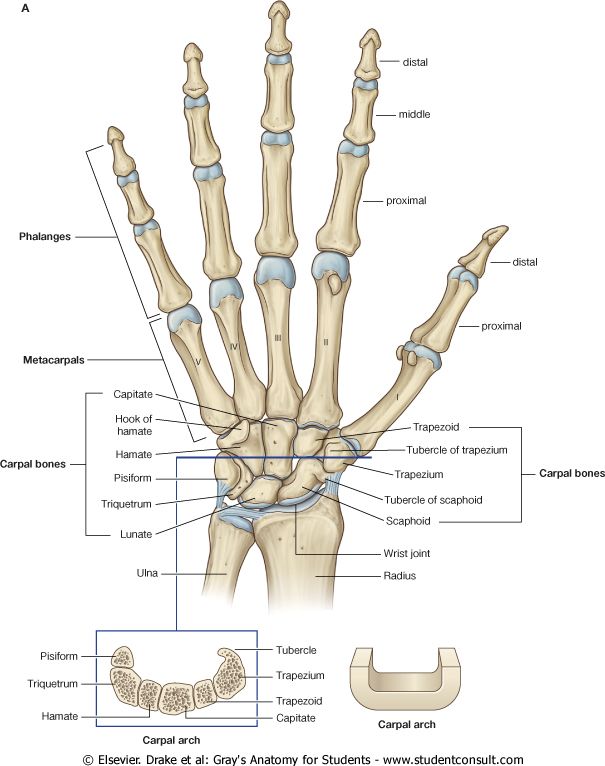

骨龄反映了你的年龄:骨龄评估 骨龄,基本上就是指你的骨头看起来多大了。随着孩子的成长,他的骨骼也在逐渐成长。这就意味着你可以通过观察儿童的骨骼,根据具备此类骨骼的儿童的平均年龄来了解这个孩子多大了。这时候你可能会想这是不是一篇考古学方面的文章:毕竟活着的小孩应该并不怎么拍 X 光。 这么想是对的,但是也不对。正常发育的话,儿童的骨龄应该在生理年龄(日历年龄)的上下 10% 区间内波动。但也有例外,例如,孩子青春期的生长突增可能会影响骨龄。因此,如果骨龄比生理年龄大几年的话,该儿童就会提前停止生长,而如果骨骼比较「年轻」的话,则可能会出现延迟的生长突增。此外,在给定身高和骨龄的情况下,你可以准确预测这个孩子的成年身高,这也可以派上一些用场:如果你的孩子喜欢篮球,你可能想知道他未来身高能否超过 7 英尺。 还有一些例外情况:骨龄和生理年龄严重不匹配是预示着身体出现问题,如成长障碍和内分泌问题等。骨龄只能告诉医生患者在特定时间时骨骼的相对成熟度,还要和其他临床指标结合才能区分出是正常生长还是生长相对提前或迟缓。连续的骨龄读数可以说明儿童的发育方向或治疗进展。通过评估骨龄,儿科医生可以诊断儿童发育过程中的内分泌和代谢紊乱问题,如骨发育不良或受营养、代谢或其他未知因素影响的生长缺陷,这可能会损害骨骺或骨质成熟。在这种生长迟缓情况下,骨龄和身高可能会有相同程度的延迟,但是经过治疗,此类儿童仍可达到正常成年人的身高。 综上所述,儿科医生常常会用 X 光照射儿童手部来评估其骨龄……所以自动化是一个很大的问题。 读手骨:从手掌和手腕评估骨龄 骨骼成熟度主要是通过骨骺中次级骨化中心的发育和骨化程度来评估的。几十年来,评估骨骼成熟度通常是根据对手骨和手腕的骨骼发育情况进行可视化评估来进行的。以下是放射科医生在查看手部 X 光片时看到的内容:

现在评估骨龄的两种最常用的技术是 Greulich-Pyle 法和 Tanner-Whitehouse(TW2)法。这两种方法都是根据成熟度指标,用左手手掌和手腕的放射图像评估骨骼成熟度,即管状骨的骨骺从骨化的最早阶段到它们和骨干融合的过程中放射影像呈现出的变化,或者是扁骨在变成成年人骨骼形状之前在放射影像上呈现出来的变化……别担心,我们在此之前也没听过这些。我们将这一过程展示在下图中: